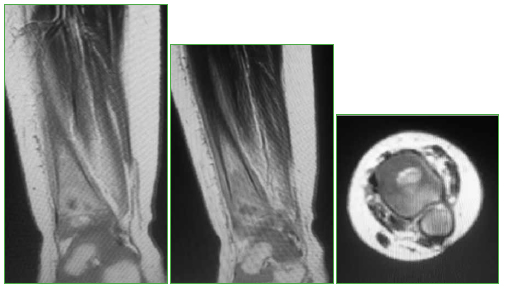

Dado el tipo de lesión revelada por las radiografías, se plantearon como posibles diagnósticos diferenciales tanto cuadros neoplásicos como una infección ósea. Por lo tanto, se decidió internar a la niña para continuar la evaluación con estudios complementarios. Se solicitaron análisis de laboratorio que arrojaron los siguientes resultados: hematocrito 33%; hemoglobina 11,5 g/dl; glóbulos blancos 9000/mm3, plaquetas 565.000/mm3, eritrosedimentación 34 mm/h y proteína C reactiva <0,5 mg/l. En la resonancia magnética de tobillo izquierdo bajo anestesia general, se observó una lesión bien definida, de 10 x 8 mm, a nivel diafiso-metafisario de la tibia distal izquierda, que comprometía cartílago de crecimiento con reacción esclerótica y edema medular óseo adyacente (Figura 2).

Figura 2.

Resonancia magnética de tobillo izquierdo, cortes sagitales y axial.